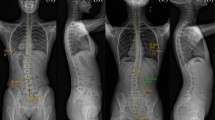

To obtain motion data for each participant, we attached a total of 14 reflective markers, each with a diameter of 14 mm, to the thorax, pelvis and feet of the subjects using double-sided adhesive tape according to a modified Helen Hayes marker protocol [25]. The locations of the reflective markers were selected by palpation on anatomical landmarks with agreement from a skilled operator and a clinician to minimize inter-experimentalist error. To obtain the thoracic segment angle, a local coordination system was created using four reflective markers attached to the seventh cervical vertebrae, tenth thoracic vertebrae, jugular notch where the clavicles meet the sternum, and xiphoid process of the sternum. The relative rotation angle was calculated with respect to the laboratory coordinate system. The sequence used to obtain the thoracic segment angle was also used to determine the pelvic segment angle with reflective markers attached to the left anterior superior, right anterior superior, left posterior superior, and right posterior superior iliac spine (Fig. 1a). To obtain the spatiotemporal variables, a total of six reflective markers were attached to the lateral malleolus, calcaneus and second metatarsal head of each foot. Vicon motion analysis system (six-camera system 460, 120 Hz, Vicon Motion Systems, Oxford, UK) and SB-InScan foot pressure measurement system (SWING BANK Ltd., Republic of Korea) were used to calculate the spatiotemporal variables and kinematic data on the thorax and pelvis [26]. Participants underwent sufficient walking practice in the laboratory, and we recorded six repetitive walking trials of a 10-m straight line, walked barefoot at a self-selected speed. Kinematic data sets were low-pass filtered with a fourth-order Butterworth filter using a cut-off frequency of 6 Hz to remove noise [27]. All walking trials were normalized through cubic spline interpolation to the 100 % gait cycle measured from one heel strike to the following heel strike of same foot. The experimental protocols to data collection were conducted by a single skilled operator and clinician.

Marker placement, coordination pattern, and consistency of the thorax and pelvis. a Marker placement of the thorax and pelvis used for the present study. b Calculation of coupling angle in the angle–angle plot. c Definition of coordination pattern. d Sample representation of coordination patterns between the thorax and pelvis in frontal plane motion. e Conceptual description of the consistency of coordination. The values of a and m indicate the consistency of coordination. Assuming an angle–angle plot with six trials, with motion expressed from the nth to the n + 1th frame as a vector, a approached 1 as the six vector directions converged, and m approached 1 as the six vector magnitudes converged. When direction and magnitude were similar, a and m both approached 1